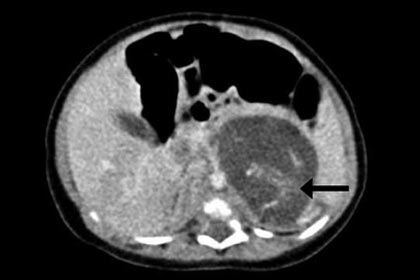

Новорожденную девочку поместили под особое наблюдение гинекологов – врачи подозревали у нее опухоль. Ультразвуковое обследование еще перед родами указало на странное утолщение в брюшной полости.

В итоге трехнедельной девочке сделали операцию: между печенью и почкой хирурги обнаружили два плода. Один из них весил 9,3 грамма, другой — 14,2 грамма, что соответствует примерно восьмой и десятой неделе беременности. У обоих младенцев нашли пуповину, соединенную с плацентоподобной массой в животе девочки.